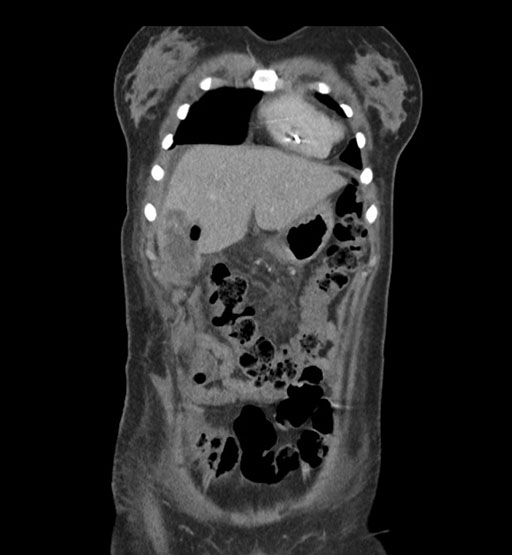

Coronal Venous